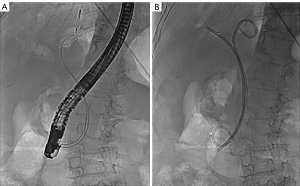

The ERCP procedure

All ERCP procedures were carried out by 6 experienced endoscopists who had cumulatively performed more than 1,000 ERCPs in the past. Preprocedure, computed tomography, and magnetic resonance cholangiopancreatography (MRCP) specifics were obtained for all the included patients and were used to confirm the diagnosis and grade of hilar block. This information was also used to preselect the intended lobe or segment for drainage (based on the liver volume being drained and ductal dilatation). Prophylactic intravenous antibiotics (third generation cephalosporins) were initiated 1 hour before the procedure and continued for 3 days. The ERCP was performed using the standard procedure noted in our previous paper (10). After bile duct cannulation had been successfully performed, a hydrophilic guidewire (Radifocus Guide Wire M, RF-GA35263M, TERUMO, Japan) was advanced through the malignant stenosis into the preselected intrahepatic dilated duct based on MRCP under fluoroscopic guidance. A papillotome was then passed over the guidewire across the stenosis until bile was aspirated (minimum 5–10 mL) to confirm the position and to decrease the intraductal pressure. ACC was then performed by injecting 10 to 15 mL of air, and the opacified ductal system was compared with the segment intended for drainage using MRCP images. If the guidewire failed to pass through the structure into the dilated duct, iodine contrast was injected to obtain a roadmap (these patients were then enrolled into the ICC group). A cytology brush (Cytomax II, Cook Medical LLC, Bloomington, IN, USA) was then used for cytopathologic examination. After the targeted bile duct was cannulated, an endoscopic nasobiliary drainage (ENBD) tube (with or without plastic stent) was placed in the bile duct. The stents used were 7- and 8.5-Fr biliary plastic stents, and the drainage tube was a 7-Fr ENBD tube. In our institution, we prefer a unilateral ENBD to the future lobe as an initial preoperative drainage procedure with hilar cholangiocarcinoma (Figure 1), a method that is accepted in Japan (7,11). For palliative treatment, a plastic stent (with or without ENBD) was implanted in the dilated bile duct (Figure 2).